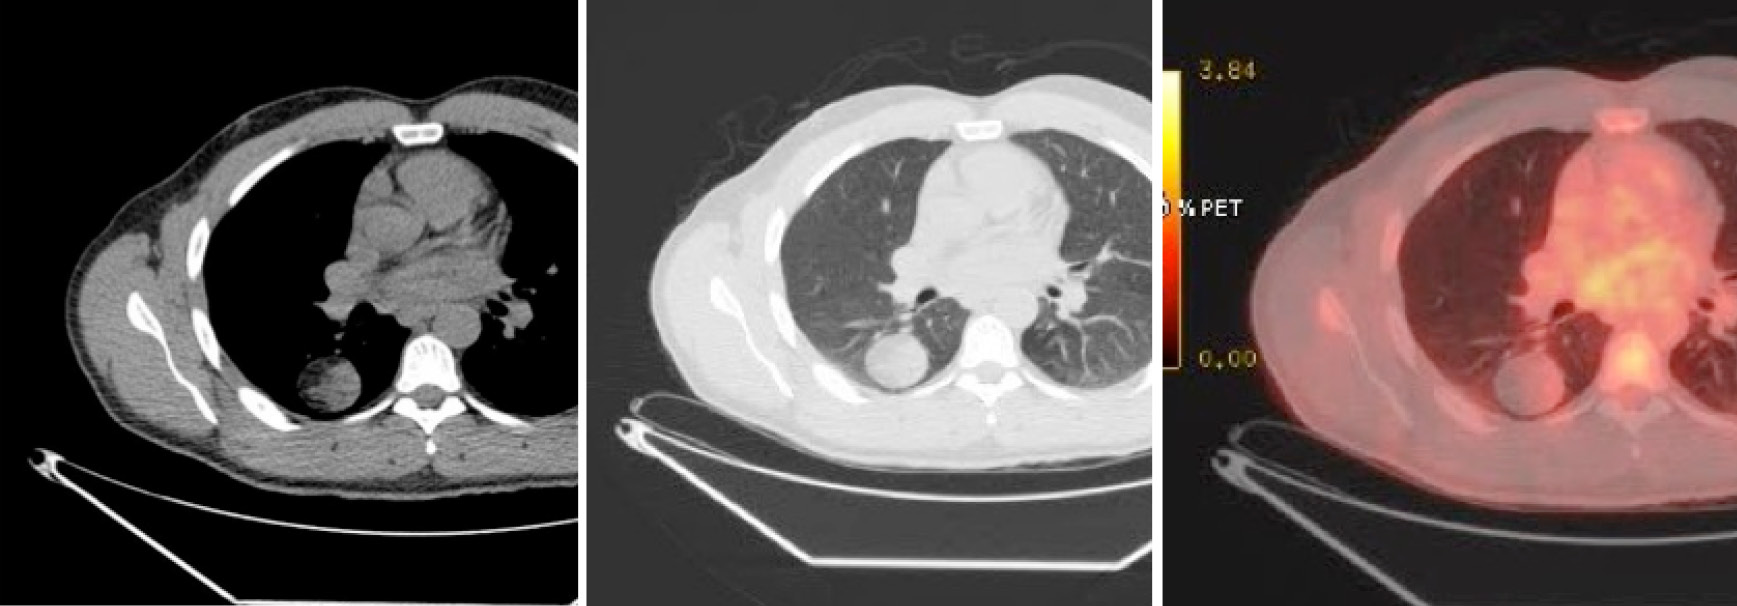

A Ct Chest Scan Showing The Corona Radiata Sign In A Patient With Download Scientific Diagram

www.researchgate.net